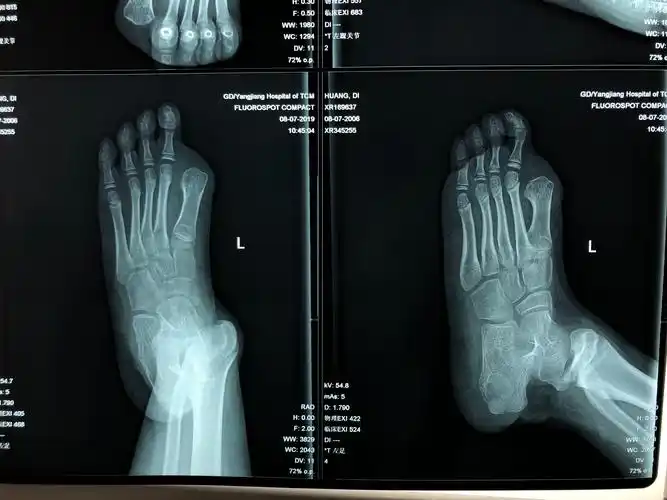

儿童踝关节损伤后畸形,该怎么处理?